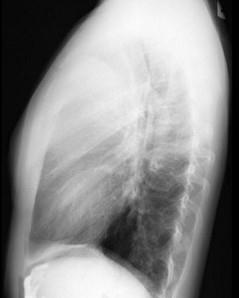

问题 18岁,男,咳嗽头晕一个月,请结合胸片和CT检查,选出最可能的诊断 ( )

选项 A、胸内甲状腺瘤 B、神经源性肿瘤 C、淋巴瘤 D、畸胎瘤 E、胸腺瘤

答案 D